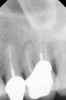

Clinical procedure: Regeneration of the endodontic pulp space is indicated for cases with very thin dentinal walls and an open apex that is more than 1 mm in diameter radiographically (Figure 4). Disinfection of the root canal system is performed using sodium hypochlorite irrigation followed by a triple antibiotic paste dressing that is left in place for 1 week. At the second visit, ethylenediaminetetraacetic acid (EDTA) is used to condition the dentin walls, which results in the release of growth factors, and bleeding is stimulated in the periapical tissues (where stem cells are located), with the aim of filling the pulp space with a stable blood clot, which would serve as the scaffold. MTA is then placed at the canal orifice in contact with the clot to protect it from coronal microleakage (Figure 5 and Figure 6). In time, the clot should be replaced with a reparative tissue of variable composition, and the root walls should continue to thicken due to the deposition of a dentin-like material on the pre-existing root dentin27,28 (Figure 7 and Figure 8).

Fig 4. Preoperative radiograph showing aggressive external root resorption and thin dentinal walls.

Figure 4